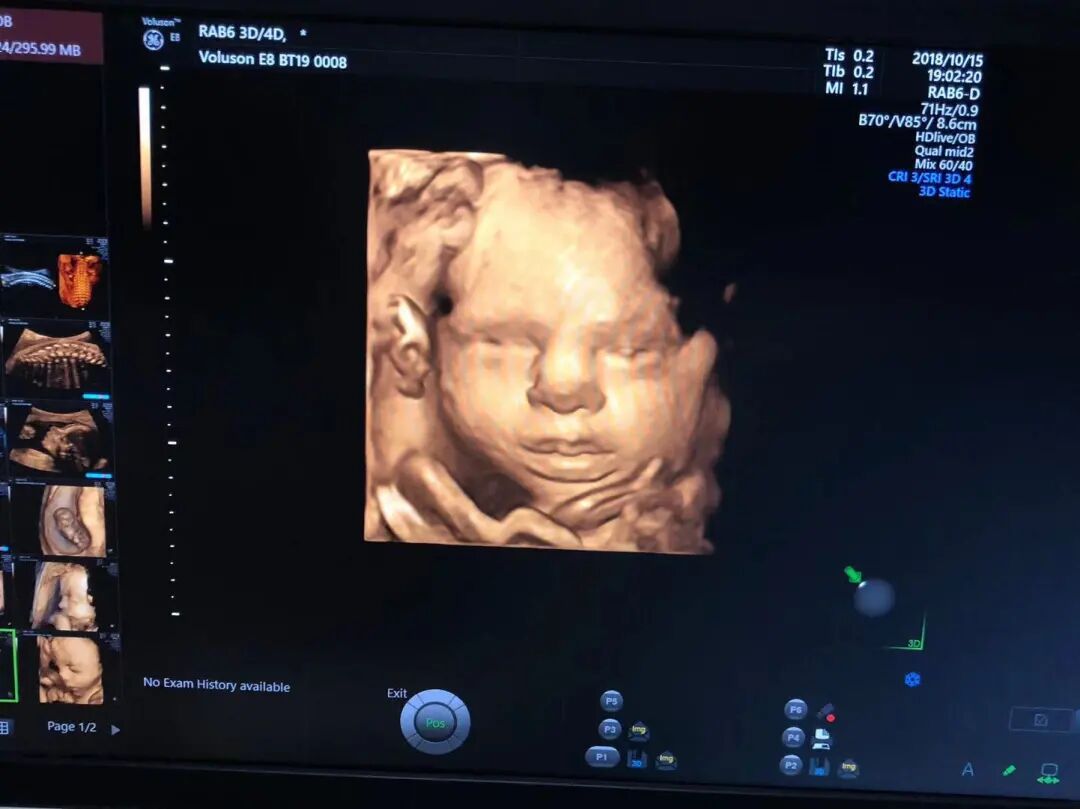

★开展四维彩超检查——拥有世界先进的超声设备,包括实时四维彩超诊断仪2台(美国GE-E8和西门子OXANA 2),2018年1月起聘请厦门三甲医院超声专家定期坐诊,为广大孕妇提供优质的胎儿检查服务。

美国GE—煊光E8四维彩超高清效果图